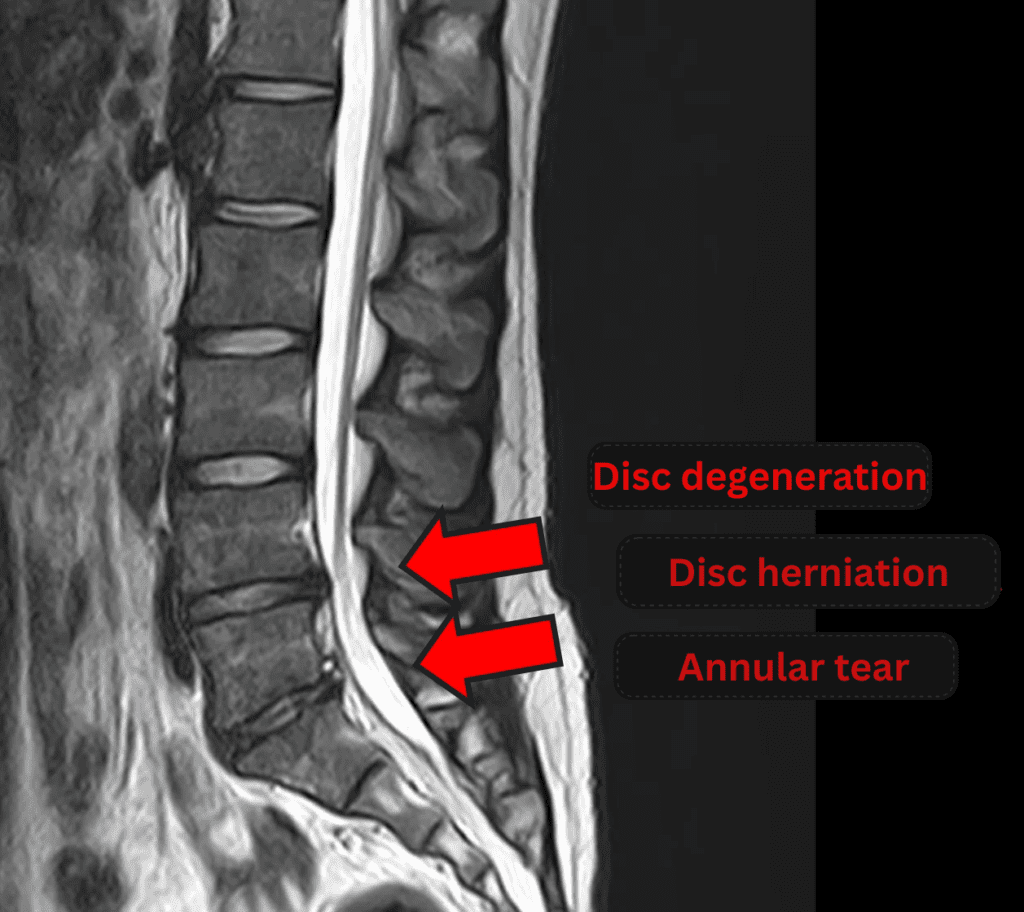

- L4/5, L5/S: Disc degeneration, disc herniation, and annular tear

The above findings were also observed on the imaging.

Compression of the spinal canal due to disc pathology at L4/5 and L5/S is considered the most likely cause of the patient’s symptoms.